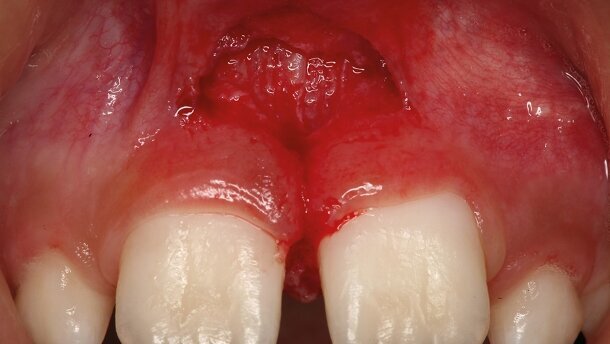

En ce qui concerne les réglages, il importe de considérer les variations de la teneur aqueuse des différents tissus tels que l’émail et la dentine, les différences de composition entre une dent temporaire et une dent permanente (entre une dent ayant fait récemment éruption et une dent plus ancienne), et d’ajuster les paramètres en conséquence.16,19 Comme indiqué précédemment, le tissu pulpaire est riche en eau et est aisément vaporisé au moyen du laser Er:YAG. Il faut donc prendre garde aux cavités profondes qui sont très proches de la cavité pulpaire (Figs. 8–10).20,21 La technologie récente du laser Er:YAG réussit très bien la vaporisation et la coagulation de la pulpe, et ne produit qu’une très faible élévation de température dans le tissu résiduel, ce qui est important pour la vitalité de la pulpe pendant une procédure de coagulation ou une pulpotomie. Le laser LightWalker (2 940 nm ; Fotona, Ljubljana, Slovénie) réglé à 5 ou 10 mJ, 15 Hz, durée d’impulsion de 300 microsecondes, pour une exposition défocalisée de 5 à 10 secondes, est très efficace pour obtenir une coagulation de la pulpe lors d’un coiffage pulpaire. Des interventions sur les tissus mous sont facilement réalisées et le laser Er:YAG ne provoque jamais de carbonisation du tissu même à des niveaux énergétiques élevés (Figs. 1–7).

Le recours à une pulvérisation d’eau et la possibilité de moduler la durée de l’impulsion, permet de réaliser différentes interventions avec une interaction thermique plus ou moins importante (le niveau thermique de l’interaction sera plus élevé lors d’une légère pulvérisation d’eau et le sera moins en cas de pulvérisation plus importante). Une gingivectomie ou une frénectomie sera réalisée en utilisant une durée d’impulsion plus longue (300–600 microsecondes) que pour une préparation cavitaire (50–100 microsecondes), et aussi une énergie différente. Lorsque le traitement porte sur plusieurs tissus au cours de la même intervention, par exemple une frénectomie labiale ou l’exposition d’une dent incluse portant sur l’os et la gencive/muqueuse, il faut prendre garde à varier les réglages selon les différents tissus.